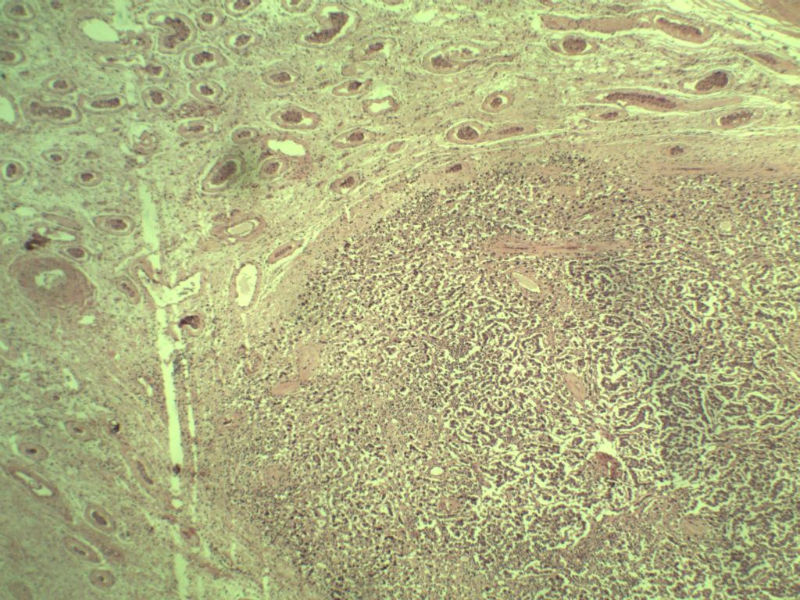

男 27岁 腹腔隐睾 5*3*2 cm, 切面灰红灰黄、实性、质中,请各位老师看看,是精原细胞瘤吗?感觉不像.腹腔隐睾图1

典型的精原细胞瘤,隐睾易恶变